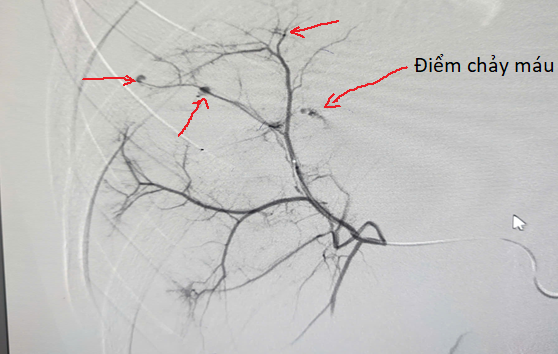

Hình ảnh sau khi chụp mạch máu của bệnh nhân (Với những điểm chảy máu được vẽ mũi tên đỏ)

Tại đây, sau khi được thăm khám lâm sàng, các bác sĩ ngay lập tức tiên lượng rằng đây có thể là một trường hợp chấn thương bụng kín nặng, bệnh nhân được chụp cắt lớp vi tính ổ bụng và không ngoài dự đoán, bệnh nhân A bị chấn thương gan độ IV (Theo phân loại AAST), có nhiều ổ chảy máu hoạt động. Đây là một trường hợp cấp cứu, nếu không can thiệp kịp thời bệnh nhân có thể bị sốc do lượng máu chảy quá nhiều, thậm chí dẫn đến tử vong. Với tinh thần hết sức khẩn trương, các bác sĩ đã lập tức đưa bệnh nhân lên phòng can thiệp mạch và tiến hành nút động mạch cầm máu chấn thương gan. Sau khi tiến hành nút động mạch gan để cầm máu, bệnh nhân đã dần ổn định và được ra viện sau vài ngày. Khoảng chục năm trước, những trường hợp chấn thương gan phức tạp như của bệnh nhân A, các bác sĩ sẽ phải phẫu thuật mổ mở vào ổ bụng để có thể cầm được máu chảy, sau mổ thời gian phục hồi và phải nằm viện rất lâu.